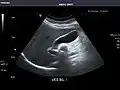

Abdominal ultrasound can be used to diagnose abnormalities in various internal organs, such as the kidneys,[1] liver, gallbladder, pancreas, spleen and abdominal aorta. If Doppler ultrasonography is added, the blood flow inside blood vessels can be evaluated as well (for example, to look for renal artery stenosis). It is commonly used to examine the uterus and fetus during pregnancy; this is called obstetric ultrasonography.[2][3]

Abdominal ultrasound is commonly used in the setting of abdominal pain or an acute abdomen (sudden and/or severe abdominal pain syndrome in which surgical intervention might be necessary), in which it can diagnose appendicitis or cholecystitis.

Kidneys: Right and left kidneys measure 11.5 cm and 12 cm in length respectively. No hydronephrosis. Small left lower pole kidney cyst.